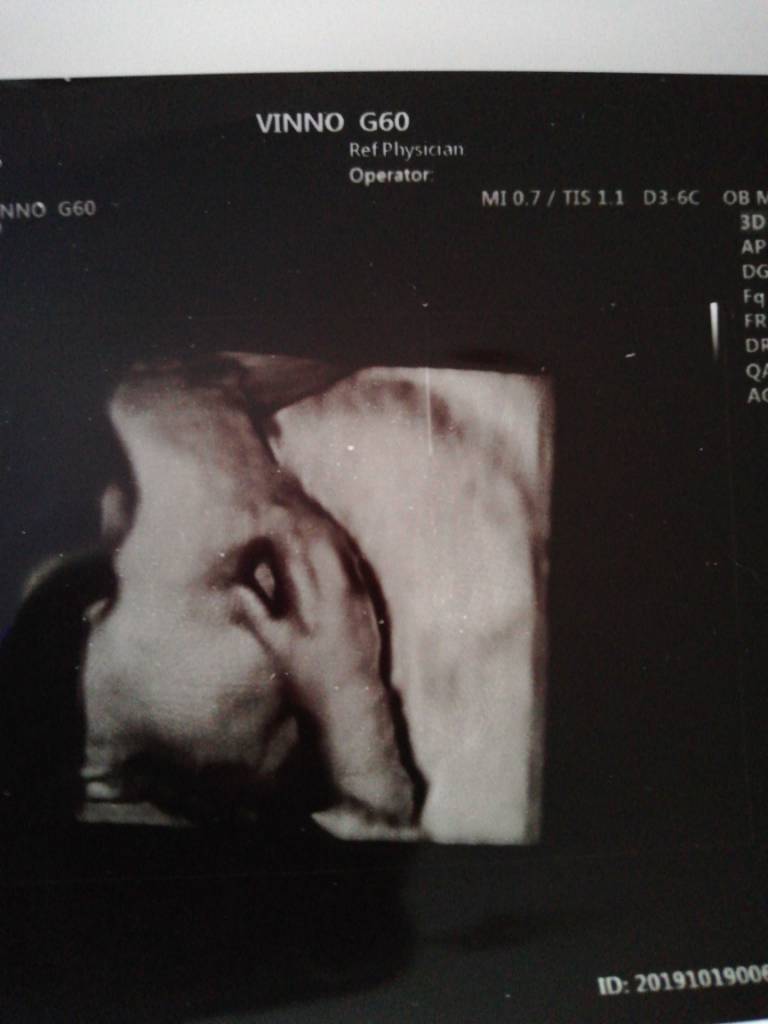

Coś wstydliwe te nasze chłopakiByłam na zdjęciu 4d masakra o 9 poszłam od 11 się zaczynało. O 9 już było 9 osób. Zrobiliśmy sobie listę ja byłam na 10. No i tak czekaliśmy z koleżanką. Wychodziłam o 14.20. Można było się zapisac na badanie usg albo na zdjęcie 4d które okazało się 3d. I robione na odczep może dlatego że za darmo. Mała miała rękę na twarzy nie chciała się pokazać za nic. A widziałam po lekarzu o ile w ogóle byl lekarzem że nie chce mu się uchwycic. Dał mi tylko takie. I potwierdził że dziewczynka i tyle. Ale była pierwsza pomoc, można było zdjęcie z brzuchem zrobić, położna laktacyjna. Zobacz załącznik 1035789

Byłam na zdjęciu 4d masakra o 9 poszłam od 11 się zaczynało. O 9 już było 9 osób. Zrobiliśmy sobie listę ja byłam na 10. No i tak czekaliśmy z koleżanką. Wychodziłam o 14.20. Można było się zapisac na badanie usg albo na zdjęcie 4d które okazało się 3d. I robione na odczep może dlatego że za darmo. Mała miała rękę na twarzy nie chciała się pokazać za nic. A widziałam po lekarzu o ile w ogóle byl lekarzem że nie chce mu się uchwycic. Dał mi tylko takie. I potwierdził że dziewczynka i tyle. Ale była pierwsza pomoc, można było zdjęcie z brzuchem zrobić, położna laktacyjna. Zobacz załącznik 1035789